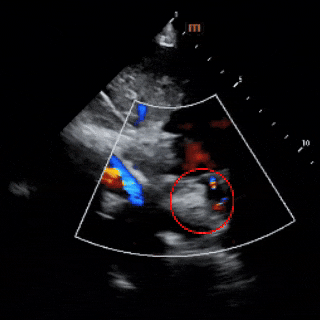

锁定后评估

彩色多普勒血流成像显示无残余分流存在

释放后评估

超声下可见封堵器形态良好,多普勒显示无残余分流,封堵成功。

出院前评估

超声所见:1、各房室腔内径正常。大动脉内径及位置关系正常。2、室间隔及左室后壁厚度及运动幅度正常。房间隔中部见封堵器回声,位置良好,CDFI:房水平未见明显分流。室间隔连续。3、CDFI示三尖瓣见小反流束;余瓣膜形态回声及启闭未见明显异常。4、心包厚度正常,心包腔内未见液性暗区。5、心功能测值正常。

超声提示:房间隔封堵器术后,封堵器位置正常。

出院前患儿心功能指标正常,肺动脉压恢复正常,二尖瓣反流消失,三尖瓣反流由术前少量转为轻微。